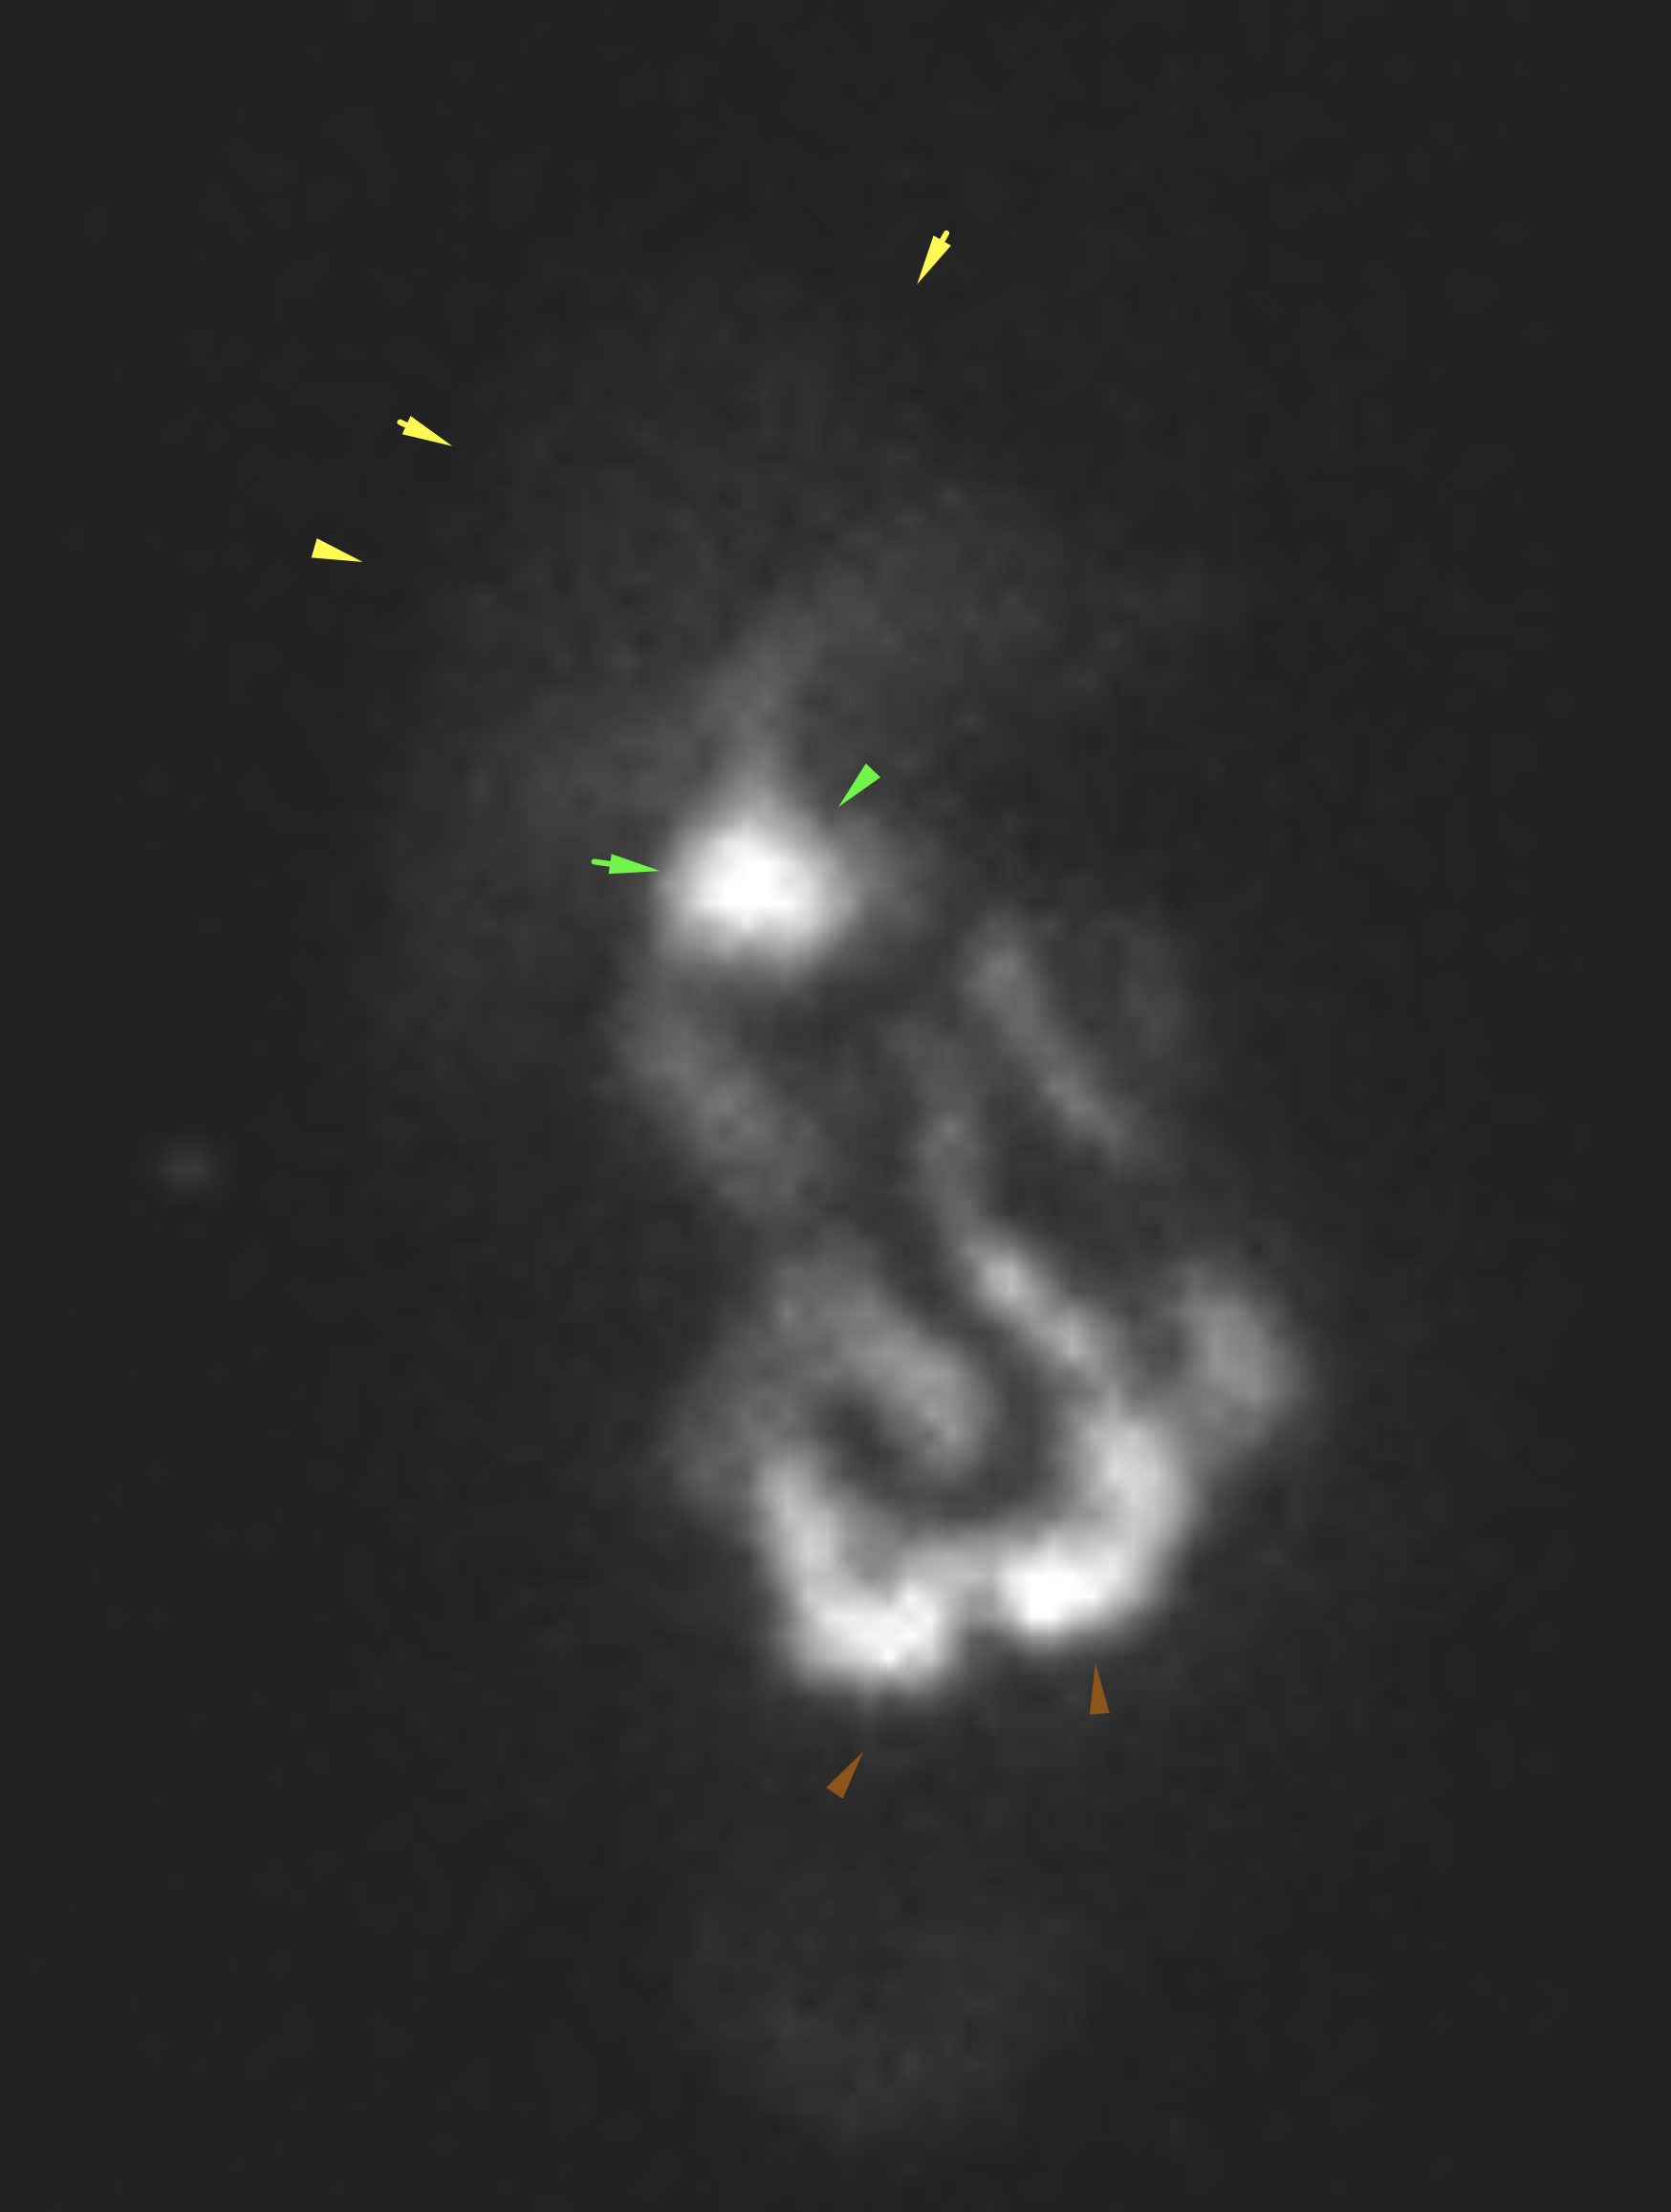

Age: 44

Sex: Male

Indication: Right upper quadrant pain

Radiotracer: Tc99m Mebrofenin

IV morphine administered at 1 hour

Sample ReportFindings consistent with acute cholecystitis.